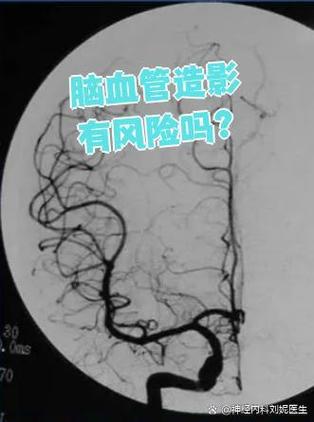

血管造影,全称是“数字减影血管造影”(DSA),是一种微创的检查技术,医生通过穿刺血管(通常是手腕或大腿的动脉),将一根细导管送到脑部血管,然后注入造影剂,在X光下实时观察脑血管的情况。

它的核心价值在于“看清楚”,就像战场上的侦察兵,而不是直接开火的士兵。